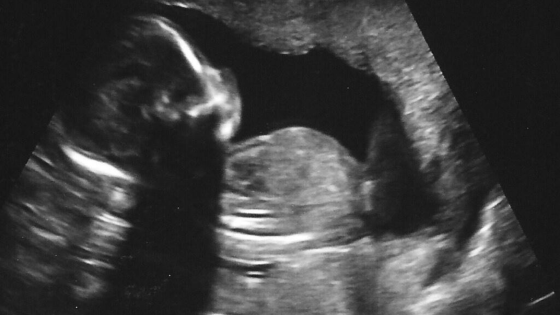

Small, barely four centimeters, that is And already reaching out to loved ones Touching them in ways not experienced before…